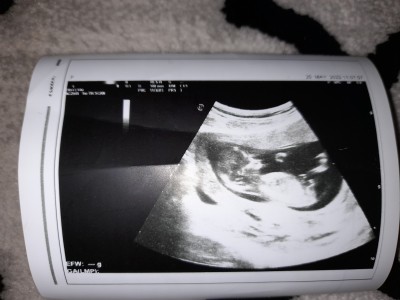

cinsiyet tahmini resimli sizce

14 haftalgiz sizce nedir

Kız bebiş canm

Senin attığın ultrason resmi gibi kızların kemik yapısı :) doktorunuz ne dedi

Kiz tahmin etti ama nasıl tatlı bisey bu

Kiz gibi geldi bana canim

bence de kiz canim :)

dikkatli baktim ve kararimi degstrdim erkk :)

bacak arasinda yukari dogru bsy gordum sanki : D

Hep tahmin yapıyoruz ama tahmin yaptıklarımız bir kere de çıkmadı cinsiyeti bu diye sen öğrenince yaz kız

Kız gibi sanki

Aslında doktor emin olmadi acısına göre kiz dedi 3 hafta sonda net soylicem dedi yazarım buraya cnm :)

Erkekkkkkkkkkkkkk